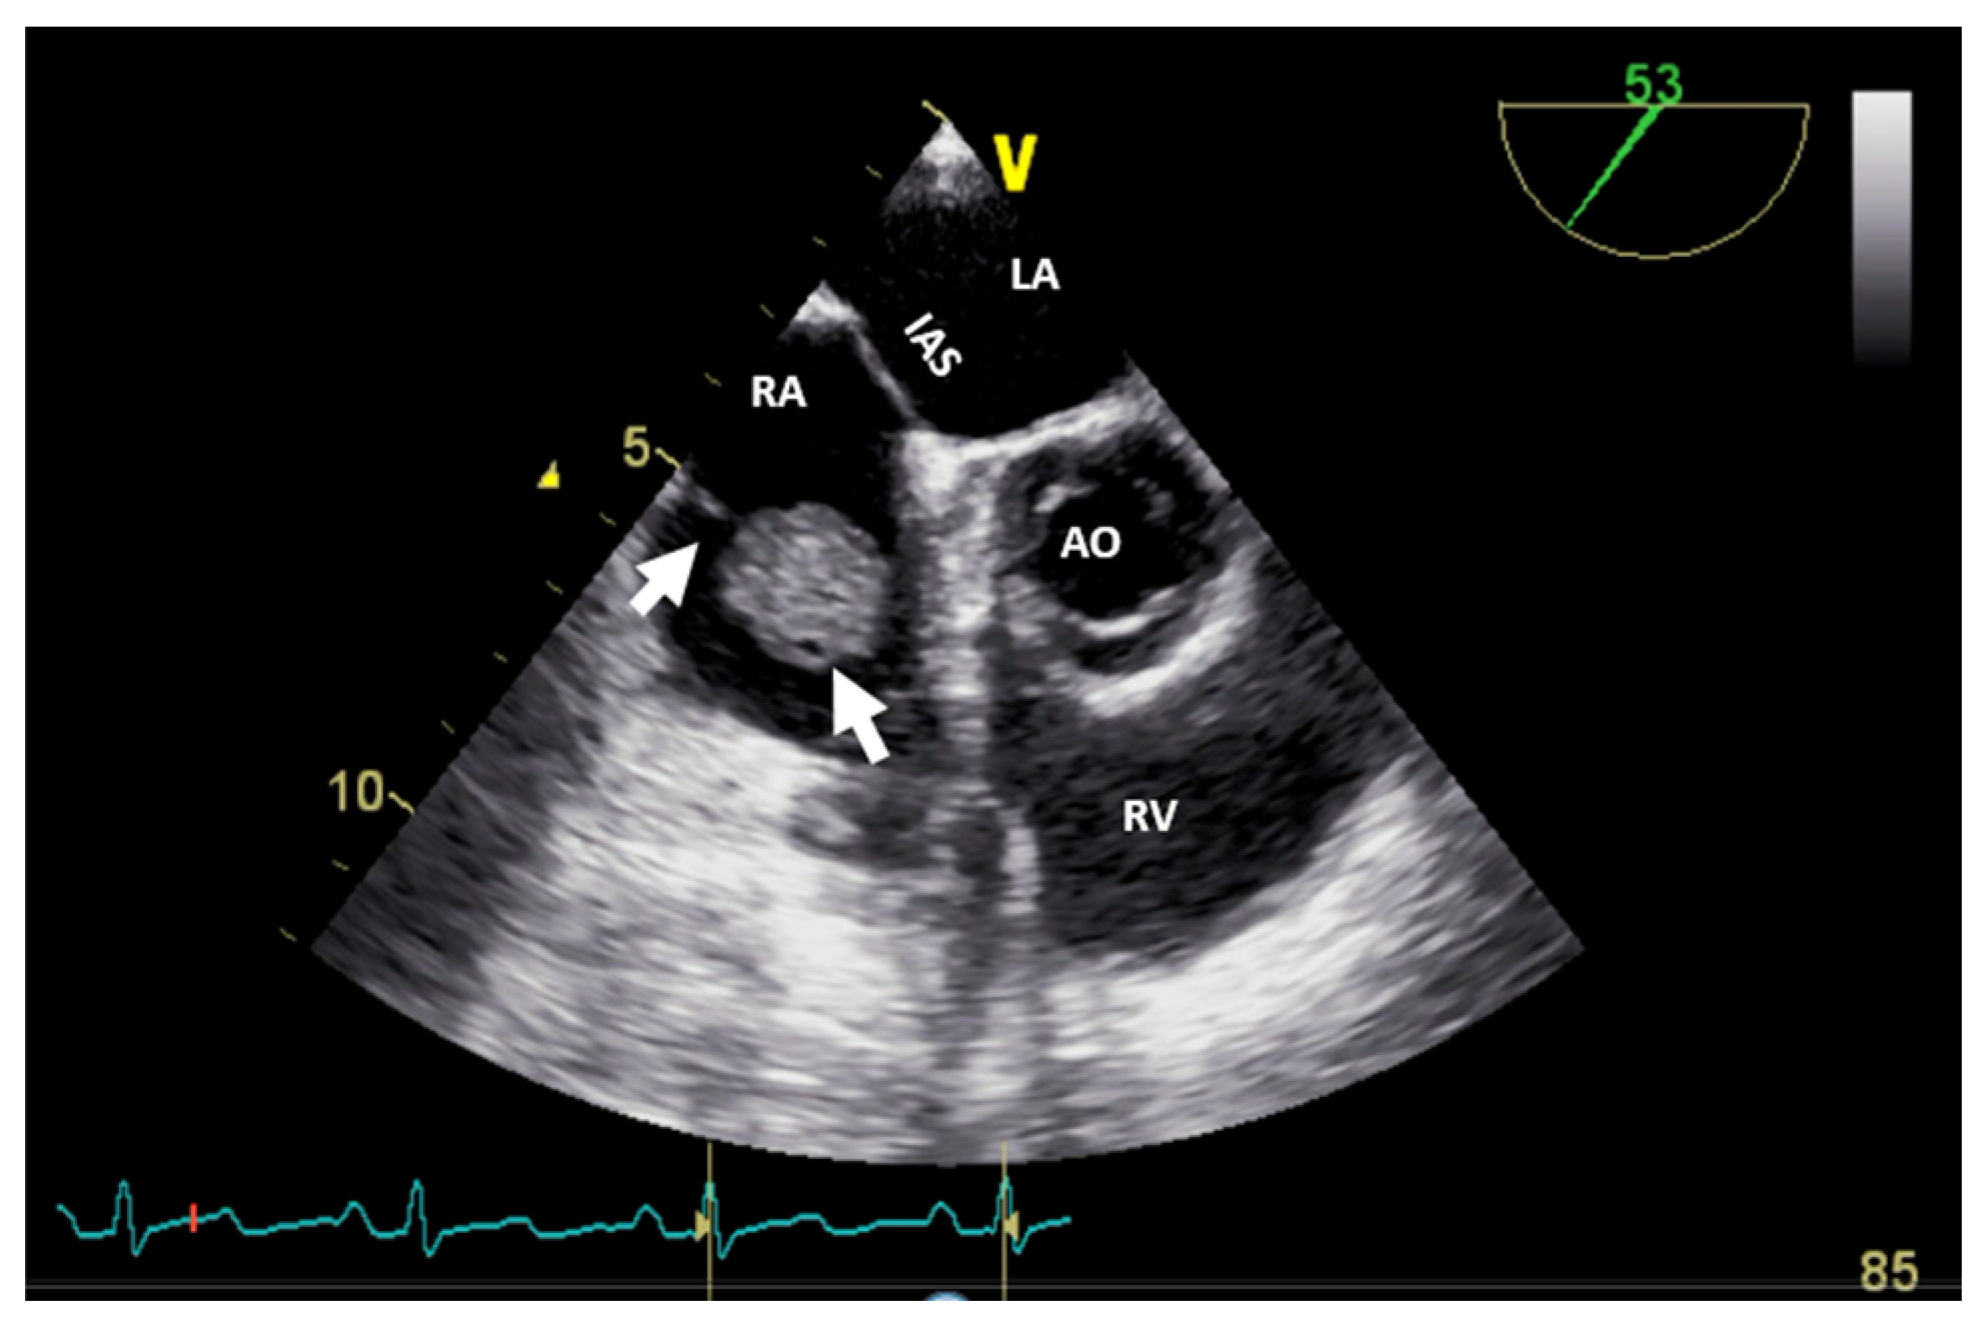

| PARAGANGLIOMA: It is associated with symptoms such as tachycardia, tremors, palpitations, flushing, hypertension, or hypotension because of excessive secretion of catecholamines. | It appears as a granular, oval, heterogeneous structure, well-delimited, with a broad base. Sometimes, adjacent structures, like the superior vena cava, can be compressed. They are highly vascular structures. | It is a well-delimited heterogeneous structure with low attenuation. In contrast CT, it is characterized by marked heterogeneous enhancement. If the margins are poorly defined, invasion or extracardiac extension can be suspected. Coronary angiography is able to assess the relationship with the tumor. | It appears on T1WI as isointense or hypointense, and on T2WI as hyperintense, heterogeneous, and with peripheral rim enhancement. | It appears positive with an intense uptake of radiotracers. |